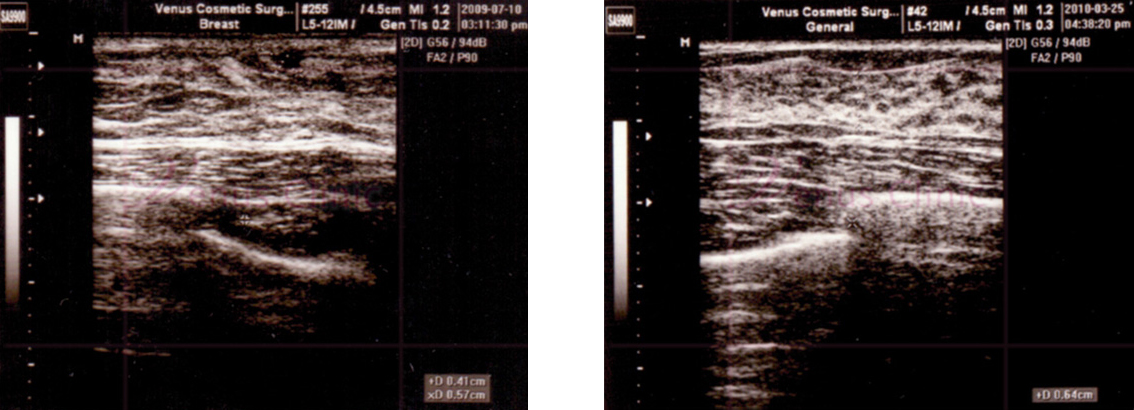

아랫사진의 왼쪽은 지방으로 이루어진 가성 여성형 유방의 초음파 사진이며, 오른쪽은 유선조직이 지방층 사이에 있는 진성 여성형 유방의 초음파 사진 입니다.

img_gynecomastia-1.jpg